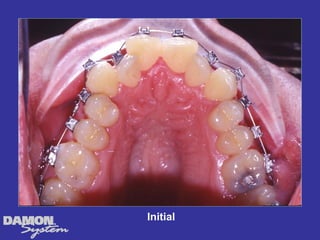

M.J. 14 yrs 6mos Class I severe crowding, deep bite, all Initial cuspids blocked out.

Treatment Planning โ€ข Ceph numbers โ€ข Model analysis โ€ข Pano X-rays โ€ข Facial analysis โ€ข Impact of growth/aging โ€ข Vestibular bone density โ€ข Tongue position/airway โ€ข How light a wire do I need to stimulate blood flow?